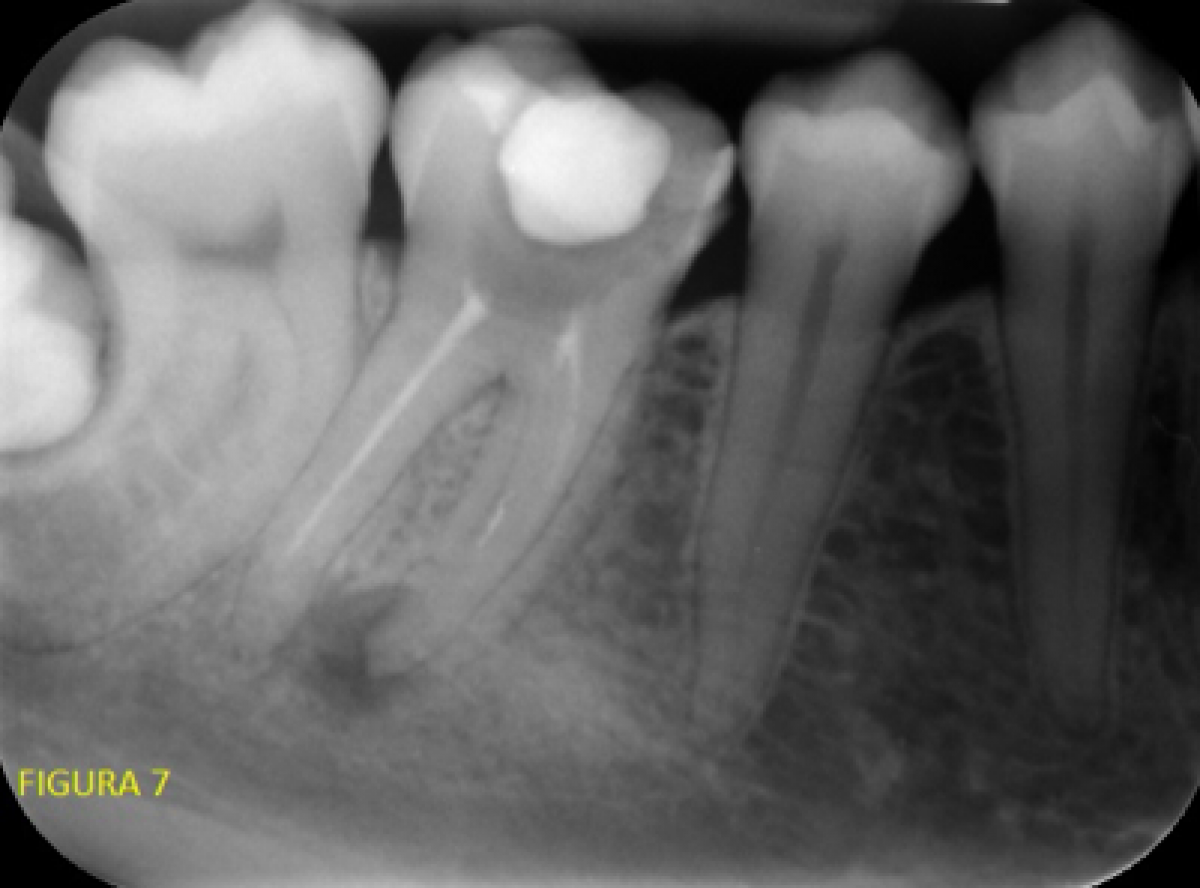

The patient came to us with painful symptoms on percussion and with increased mobility at 3.6. As a first-level analysis, we performed an intraoral X-ray with the Rinn alignment system.

Highlighted features included an area of radio-transparency on the mesial root of zone 3.6, no alterations on the apex of the distal root, earlier root canal treatment evidently short on both roots.